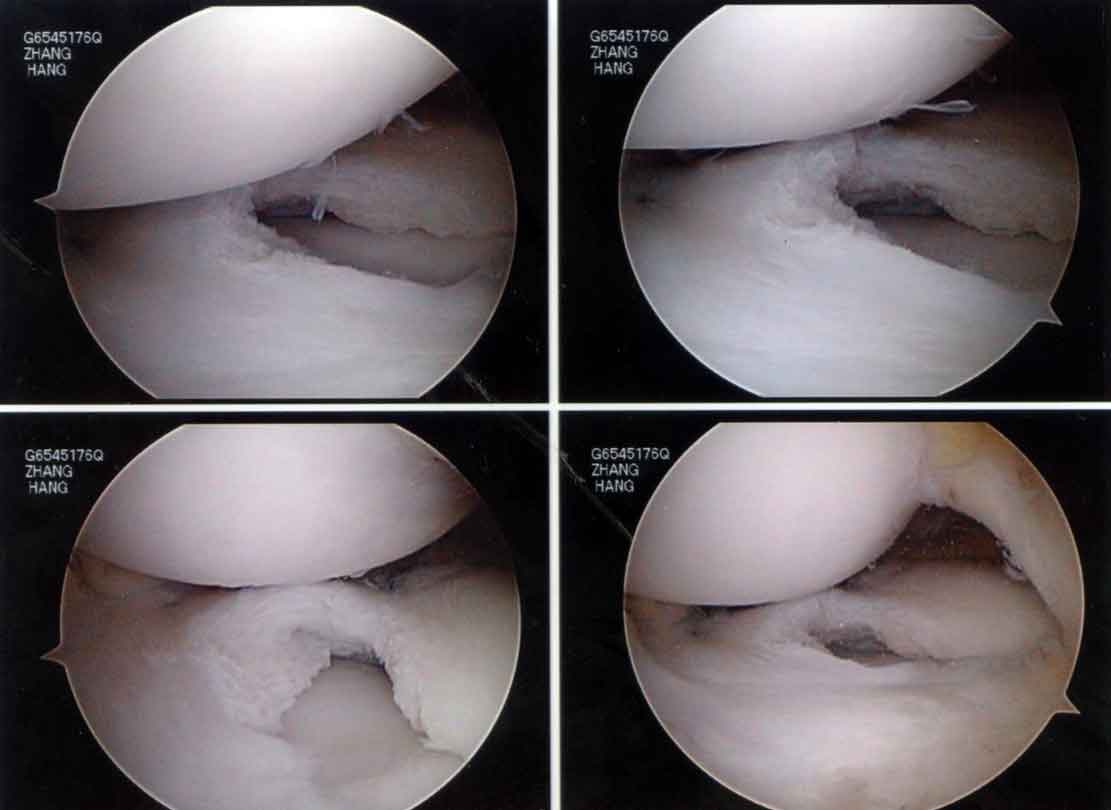

The final reconstructed discoid lateral meniscus looked like this:

The patient did well and got back to her work without further problems.